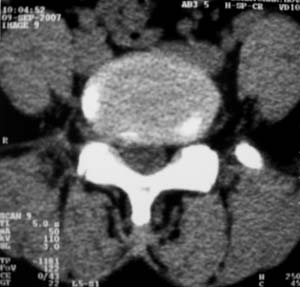

标题: CT9676:女,34岁,腰5骶1右侧神经根增粗?请各位老师会诊! [打印本页]

标题: CT9676:女,34岁,腰5骶1右侧神经根增粗?请各位老师会诊!

女,34岁,腰背部及右下肢酸痛两年余.

神经源性肿瘤可能性大;1椎间孔较对侧明显大,2相应层面似见椎间盘边缘.建议作mri.

神经源性肿瘤?突出?椎间盘扫描的层厚太厚了。建议mri或薄层扫描

对比观察

[emb10]为什么说是椎间盘病变呢?还有椎间盘脱出有脱向头端方向的吗?

腰间盘突出是有的,右侧椎间孔增大,还是做个mri吧。

右侧椎间孔显宽,考虑为体位不对称所致.扫描层厚偏厚了,考虑孔间型间盘突出.